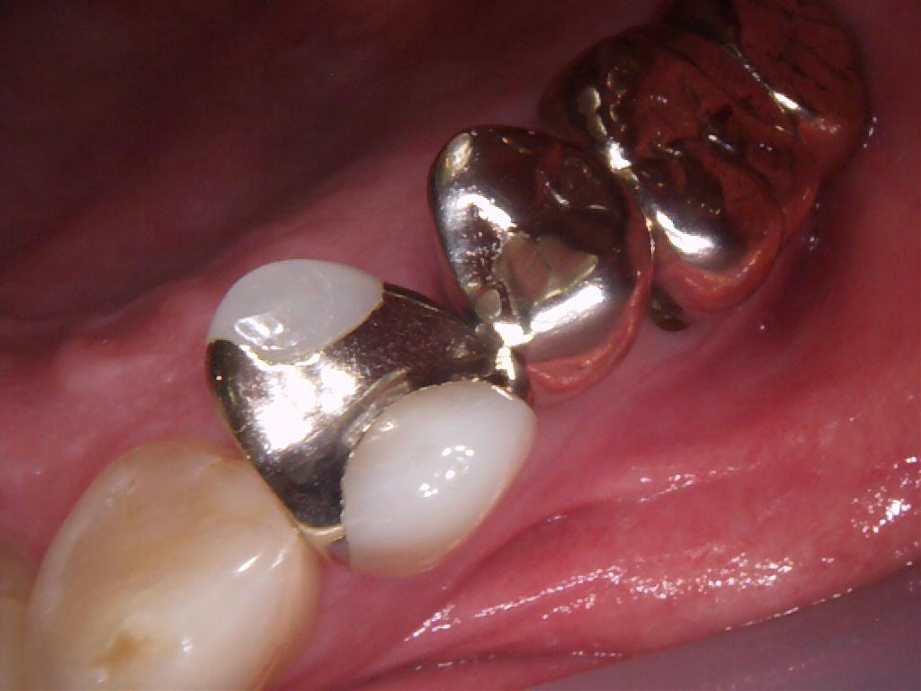

治療前

-

治療後

- 治療名称

- 右下56番パーシャルデンチャー部のインプラント治療

- 患者の症状

- 右下56番にパーシャルデンチャーを装着しており機能及び審美的に問題を抱えている。

- 治療内容

- まず、CT撮影による精密な骨の分析・治療計画を立てガイドを使いインプラント埋入しインプラントが骨と結合するのを待つ間に仮の歯を入れます。その後本歯を作成して装着しました。

- 治療期間・回数

- インプラント埋入からジルコニアセットまで三か月半

- 費用

※自由診療となります - ■総額:¥660,000(税込み) ■内訳:埋入(ガイド込み)¥200,000×2、仮歯¥20,000×2、被せ物¥80,000×2